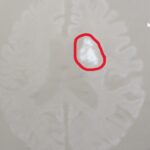

PTP誤飲

救急科

90代の当院かかりつけの方が くすりと一緒に、アルミの包装も飲んでしまい 受診されました。 CTで白く見えているものがPTPです。 もしこの方のかかりつけが、糖尿病しかみないクリニックだったら この方は、そこにはいかないでしょう。 病院を探さないといけません。 またそのまま様子をみてしまうこともあるでしょう。 最悪、腸に穴があいてしまいます。 総合診療かかりつけ医であれば、 患者さんは困ったらす...